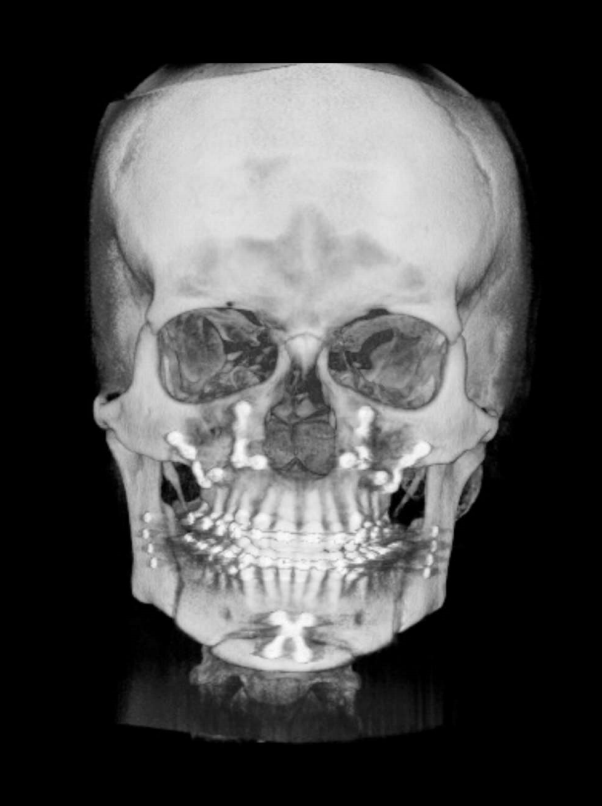

TC de face (do Hióide à Glabela), reconstrução 3D do tecido ósseo, radiografia panorâmica, telerradiografia lateral com traçado, cortes transversais e axial de maxila e mandíbula e arquivo DICOM- entregue em pasta de Pvc.

TC de face (do Hióide à Glabela), reconstrução 3D do tecido ósseo, radiografia panorâmica, telerradiografia lateral e frontal com traçado, cortes transversais e axial de maxila/mandíbula e arquivo DICOM – entregue em pasta de Pvc.

TC de face (do Hióide à Glabela), reconstruções 3D do tecido mole/ósseo/vias aéreas, radiografia panorâmica, telerradiografia lateral e frontal com traçado, cortes transversais e axial de maxila/mandíbula, ATM e arquivo DICOM – entregue em pasta e caixa de Pvc.